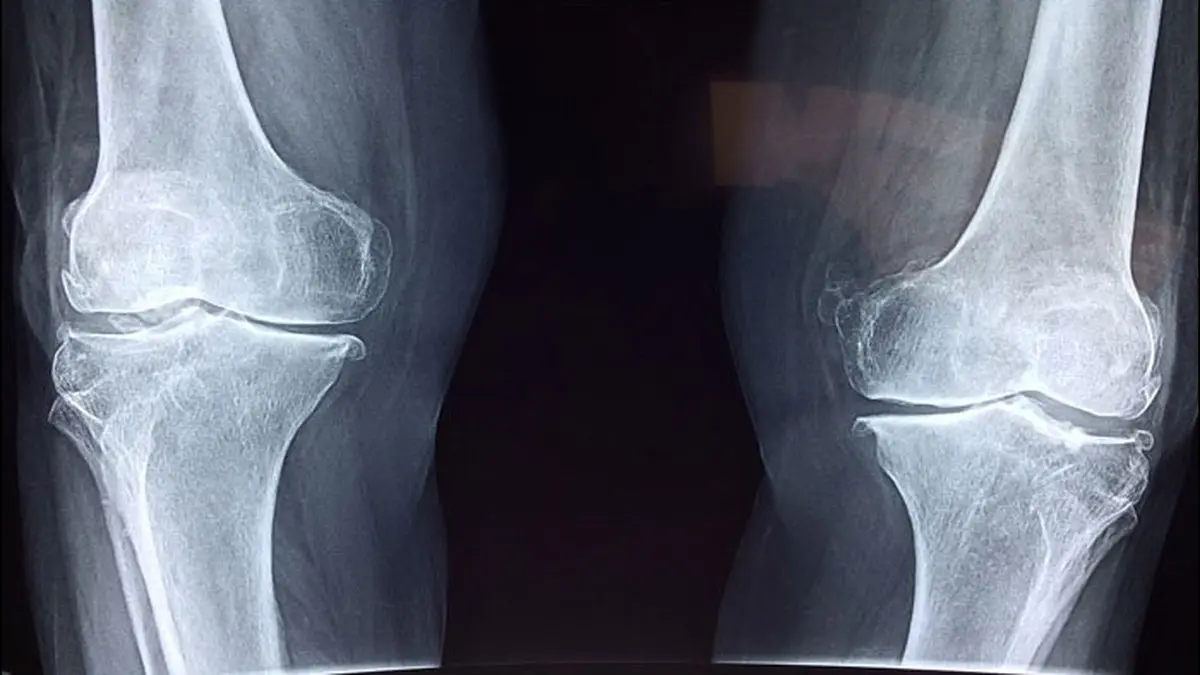

نانو الیاف های آرامید چارچوب مواد را تولید می کنند، در حالیکه PVA هنگامی که تحت کشش یا فشرده سازی قرار می گیرد آب را در پشت شبکه به دام می اندازد درست همانند عملکرد غضروف های طبیعی را ایجاد می کند که باعث می شود بتوان با فشار بر زانو حرکت کرده و راه برویم.